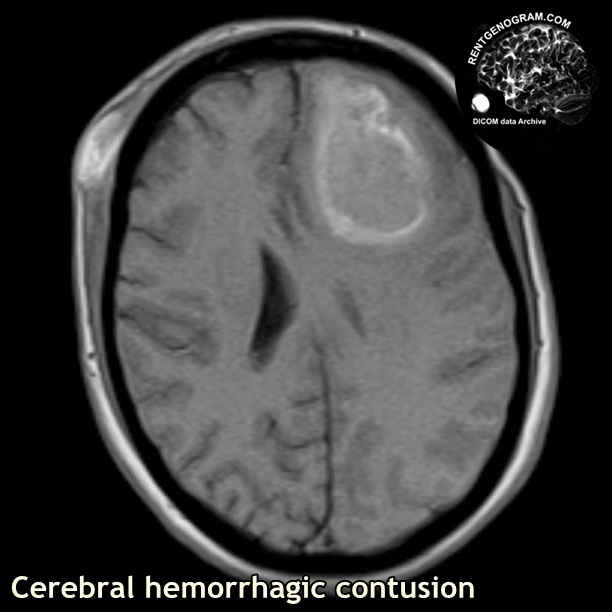

Медицинские аспекты и диагностика субдуральной гигромы мозга